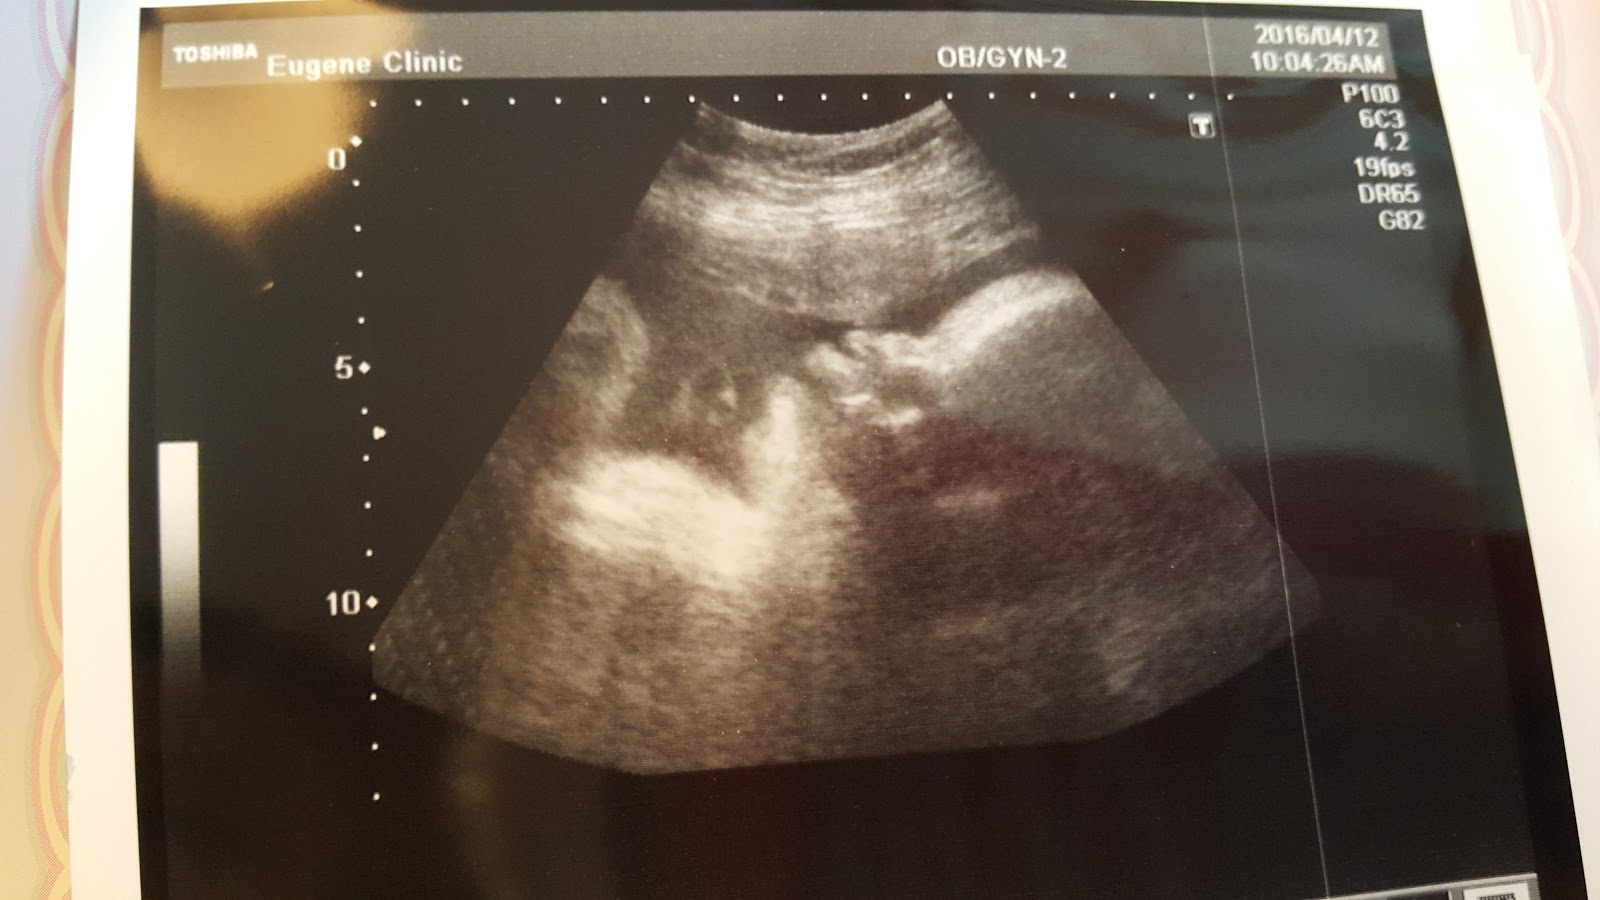

這是昨天(38w+4)拍的照片,覺得好看,拿來放首圖!:P

Haru baby的側臉,一如往常的可愛!(發射愛心:))

量了Haru baby的大小,醫生問上週量多少,上週是2840g

這週,醫生左量右量說,歐~怎麼突然大那麼多,我看到螢幕上的體重也有嚇一跳,這一週Haru baby居然是3170g,還是醫生量很久下的結果,本來螢幕上還跳出3200g多的數字

一週的時間,多了330g,大太多啦!